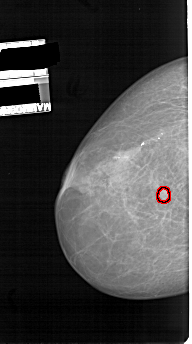

A_1114_1.RIGHT_CC

RIGHT_CC LINES 5236 PIXELS_PER_LINE 3106 BITS_PER_PIXEL 12 RESOLUTION 43.5 NON_OVERLAY